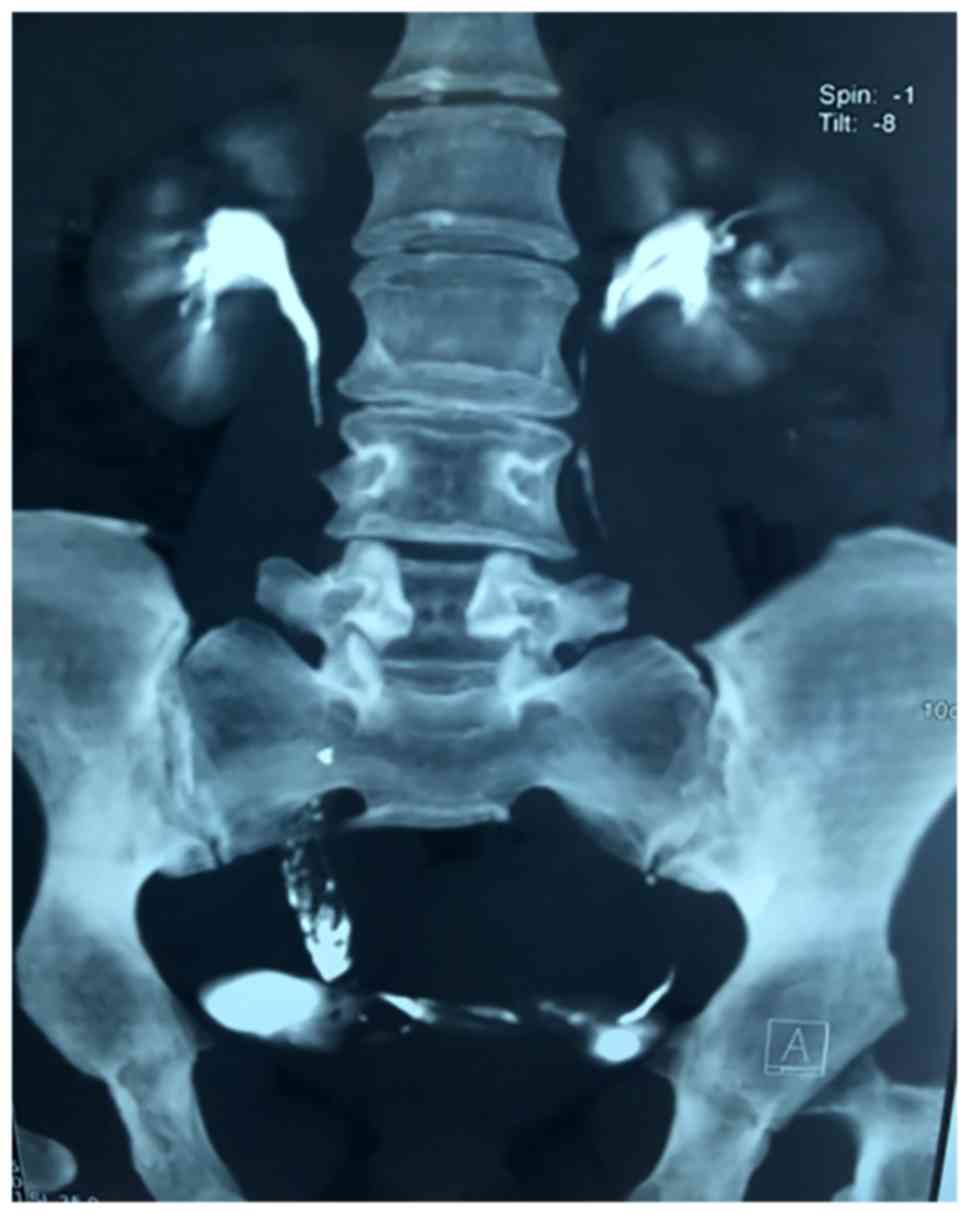

Ureteroscopic assessment was performed under general anaesthesia and revealed a pedunculated tumor (~15 cm in length) arising from the lower segment of the right ureter, with a smooth surface, with the base of the tumor located ~13 cm from the ureteral orifice. The tumor macroscopically resembled a long grape. As we unable to find the upper ureteral orifice, the ureteroscope and guidewire could not pass through the base of the tumor. A small piece of tumor was resected by Holmium laser for histopathological examination and a Double-J stent was inserted, with the upper end of the stent located in the base of the tumor. Resectoscopy was then performed to incise the portion of the polyp protruding into the bladder. The histological examination of these two bioptic specimens suggested that the tumor was a fibroepithelial polyp. Kidney-ureter-bladder imaging was then performed, which revealed that the Double-J stent was folded and twisted in the fifth lumbar plane (Fig. 4).

Figure 4.

Kidney-ureter-bladder ultrasound, showing the Double-J stent folded and twisted in the fifth lumbar plane.